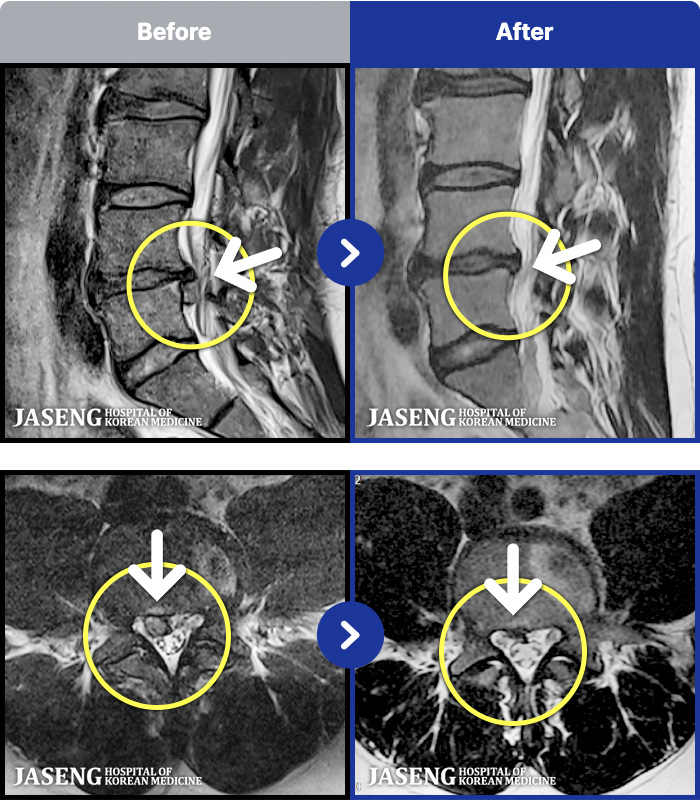

MRI ġ

MRI ũ ʸ Ȯϼ.